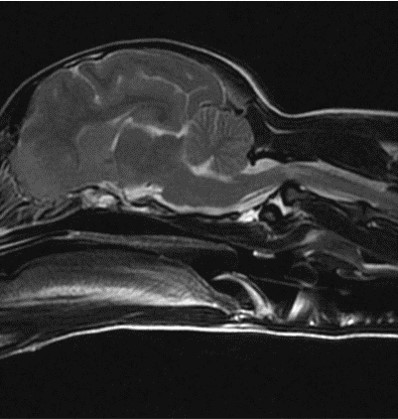

MRI 검사

자기공명영상촬영 (MRI, Magnetic Resonance Imaging) 자기에너지를 이용하여 영상을 획득하기 때문에 방사선의 발생 없이 사람과 동물 모두에게 보다 안전한 영상 기법입니다.

MRI의 경우 특히 뇌와 척수의 신경계와 같은 연부조직의 영상화에 특화되어 있어 다른 영상 기법보다 뛰어난 해상도를 나타냅니다.

건국대학교 영상진단의학과에서는 1.5 Tesla의 최신 자기공명영상촬영장치를 통해 높은 수준의 해상도를 제공하고 추가적으로 환자에게 맞는 다양한 검사 sequence가 가능하여 보다 정밀한 진단을 위해 노력하고 있습니다.

대표질환

- 두경접합부 질환

- 디스크 질환

- 척수 질환

- 척추 골절

후두골이형성,키아리 기형 -

척수공동증 -

AAI

디스크질환 -